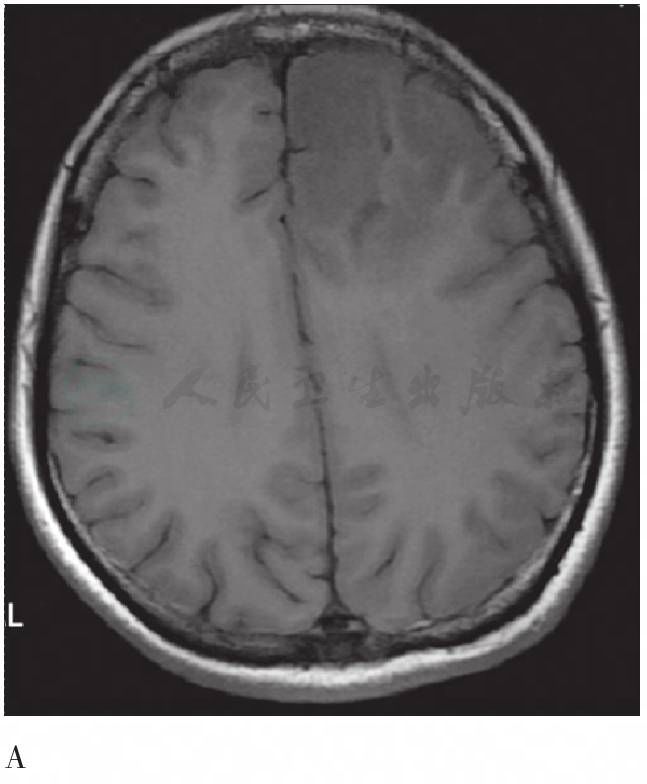

图4 头MRI平扫及增强横断层图

A. 左额病变T1WI;B. 同A层面T2WI;C. 同A层面增强;D. 右颞病变T1WI;E. 同D层面T2WI;F. 同D层面增强。MRI示左额不规则稍长T1、稍长T2信号肿块影,增强未见明显强化;右颞局部皮层增厚,可见团块状稍长T1、长T2信号影,增强未见明显强化

其他影像学图像表现:头MRI平扫示左额不规则混杂信号肿块影,边界不清,呈稍长T1、稍长T2信号,其内可见片状长T1、长T2信号影,左侧侧脑室前角受压变形,大脑镰前部向右侧移位。右侧颞叶局部皮质增厚,可见团块状稍长T1、长T2信号影,累及皮质下白质,邻近脑质受压内移。MRI增强左额及右颞病变均未见明显强化,考虑多中心胶质瘤。